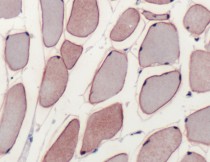

anti-Dysferlin antibody for IHC-Formalin-fixed paraffin-embedded sections,Western blot and Human

| 应用 | IHC-P, WB |

| 应用说明 | IHC-P: Antigen Retrieval: Boil tissue section in 10mM citrate buffer, pH 6.0 for 10 min followed by cooling at RT for 20 min. Incubation Time: 10 min at RT. * The dilutions indicate recommended starting dilutions and the optimal dilutions or concentrations should be determined by the scientist. |

| 阳性对照 | Skeletal Muscle, Human Skeletal Muscle |

| 背景介绍 | Dysferlin is the protein product of the 2p13 gene that is defective in patients with Limb-Girdle Muscular Dystrophy type 2B (LGMD2B) and Miyoshi Myopathy (MM). Dysferlin is normally localized to the muscle plasma membrane. In patients with LGMD2B and MM, immunoreactivity to dysferlin is severely reduced or lost, depending on the type of mutation. |